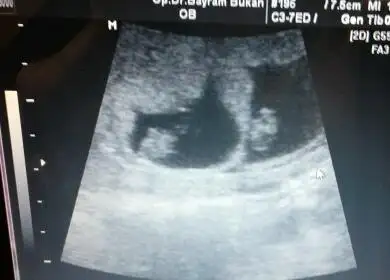

Kizlar benim simdi bebek daha buyuk ama bu ilk ultrasyondaki görüntü karindan tahminleriniz nedir acaba

aaaa sevindim.canim gozunuz aydin benim ikizler 8+2 usg paylastim sen ne diyorsun canimcanım kıza benzettim ben bunu hem kese hem konum olarak. bi önceki ultrason varsa ona bakiyim daha küçükken. bu arada ablamında bebiş gözüktü çok şükür :) ama onunki tek çıktı ikiz değilmiş.

Canim kiza benzettim ben hem kese hem bebegin konumu kiza benziyor. Tabi bizimki sadece bi tahmin.Eki Görüntüle 1807457 Eki Görüntüle 1807458 burda 8 hafta 3 cü günümüz dü